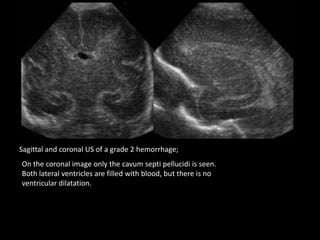

Sagittal and coronal US of a grade 2 hemorrhage;

On the coronal image only the cavum septi pellucidi is seen.

Both lateral ventricles are filled with blood, but there is no

ventricular dilatation.

Sagittal and coronalUS of a grade 2 hemorrhage; On the coronal image only the cavum septi pellucidi is seen. Both lateral ventricles are filled with blood, but there is no ventricular dilatation.